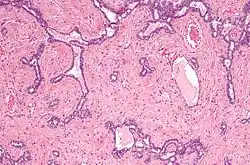

Rete testis

Le rete testis est un réseau de canaux des testicules issus des tubes séminifères droits dans le mediastinum testis.

Les canaux du rete testis s'écoulent dans les canaux efférents, qui passent dans la tête de l'épididyme. À ce niveau, le rete testis ne contient que des cellules de Sertoli, puisque tous les spermatozoïdes se trouvent dans la lumière des tubes séminifères.